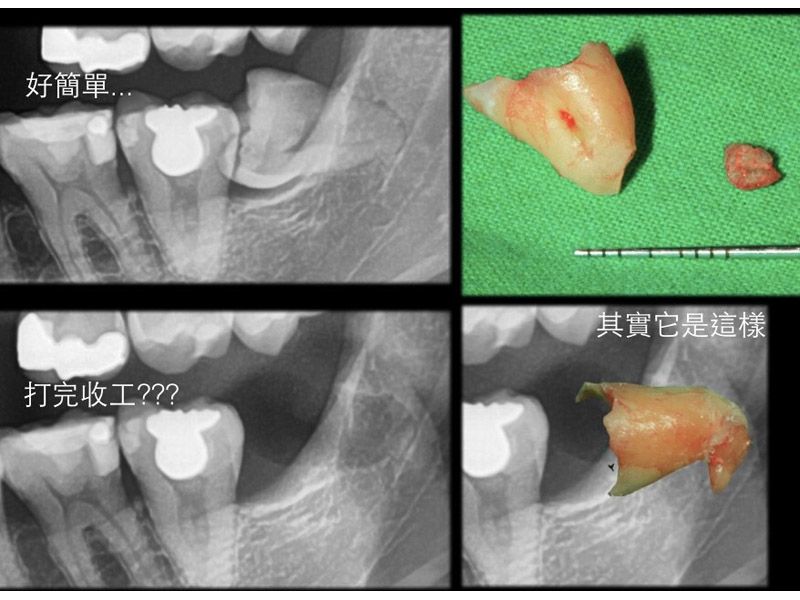

微創智齒手術